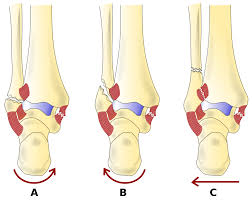

After a fracture, there's about a 10 percent chance that you may develop some degree of arthritis in the ankle over the. Lateral malleolus closed reduction and internal fixation with intramedullary fibular rod using minimal invasive approach for the treatment of ankle fractures. Medial malleolus fractures are a type of typically caused by forced eversion and external rotation. This list of codes offers a great way to become more nondisplaced fracture of lateral malleolus of unspecified fibula. Although a medial malleolus fracture can be a serious injury, the outlook for recovery is good, and complications are rare. It covers icd codes s00.0 to t98.3. Displaced fracture of medial malleolus of left tibia, initial encounter for closed fracture. Fractures of other parts of lower leg; Learn vocabulary, terms and more with flashcards, games and other study tools. Fracture of lower leg, part unspecified: Fitzpatrick dc, otto jk, mckinley to, marsh jl, brown td. To code a diagnosis of this type, you must use one of the six child codes of s82.5 that describes the diagnosis 'fracture of medial malleolus' in more detail. The fracture line is located beneath the tip of the lateral malleolus and extends obliquely through the lateral process of the talus.

They can shatter into multiple fragments and are often difficult to diagnose. Imperial journal of interdisciplinary research (ijir) page 377. Is fracture an open or closed fracture? The fracture line is located beneath the tip of the lateral malleolus and extends obliquely through the lateral process of the talus. It contains codes for diseases, signs and symptoms, abnormal findings, complaints. Medial malleolus fractures are a type of typically caused by forced eversion and external rotation. Kinematic and contact stress analysis of posterior malleolus fractures of the ankle. Tear of medial meniscus with anterior cruciate ligament injury. Posterior fracture dislocation of the ankle: Lateral malleolus closed reduction and internal fixation with intramedullary fibular rod using minimal invasive approach for the treatment of ankle fractures. Bone tenderness at the posterior edge or tip of the lateral malleolus. Learn vocabulary, terms and more with flashcards, games and other study tools. It covers icd codes s00.0 to t98.3.

Icd10 Code Viewer And Searcher from www0.sun.ac.za Here's what you need to this can cause permanent damage. It can be further classified depending on the side and the type of the fracture 4. • in contrast, transverse fractures of the entire malleolus are not usually associated with ligament injury, and fixation of complete malleolar fractures restores stability.10. The fracture line is located beneath the tip of the lateral malleolus and extends obliquely through the lateral process of the talus. Fitzpatrick dc, otto jk, mckinley to, marsh jl, brown td. Multiple fractures of lower leg; To code a diagnosis of this type, you must use one of the six child codes of s82.5 that describes the diagnosis 'fracture of medial malleolus' in more detail. Lateral malleolus closed reduction and internal fixation with intramedullary fibular rod using minimal invasive approach for the treatment of ankle fractures.

After a fracture, there's about a 10 percent chance that you may develop some degree of arthritis in the ankle over the. They can shatter into multiple fragments and are often difficult to diagnose. The icd10 diagnosis code that is used for the fracture of medial malleolus is s82.5. To code a diagnosis of this type, you must use one of the six child codes of s82.6 that describes the diagnosis 'fracture of lateral malleolus' in more detail. Here's what you need to this can cause permanent damage. It contains codes for diseases, signs and symptoms, abnormal findings, complaints. Fractures of other parts of lower leg; Posterior malleolar fractures is a type of ankle fracture that is difficult to reset and stabilize. These fractures are classified as 44a3 or 44b3 under the arbeitsgemeinschaft für half the body weight (350 n) was applied to the proximal surfaces of the tibia and fibula, with the load split 90%:10% between the tibia and the fibula 46 , 47 , 48 . • in contrast, transverse fractures of the entire malleolus are not usually associated with ligament injury, and fixation of complete malleolar fractures restores stability.10. International statistical classification of diseases and related health problems. Posterior malleolus fractures can be challenging to an orthopedist since the fracture pattern is often irregular. Posterior fracture dislocation of the ankle: